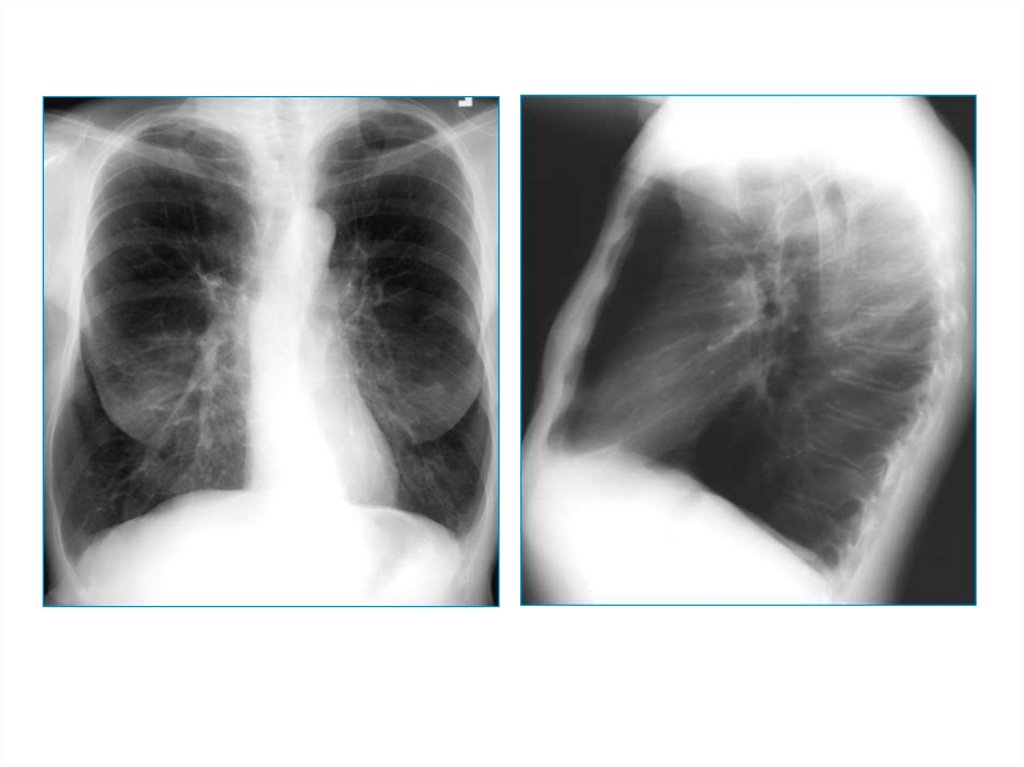

4. Повышенная воздушность

Эмфизема легких – признаки:

• увеличенные легочные поля

• низкое стояние диафрагмы

• грудина смещена кпереди, большое

ретростернальное пространство (на боковом

снимке)

5.

6.